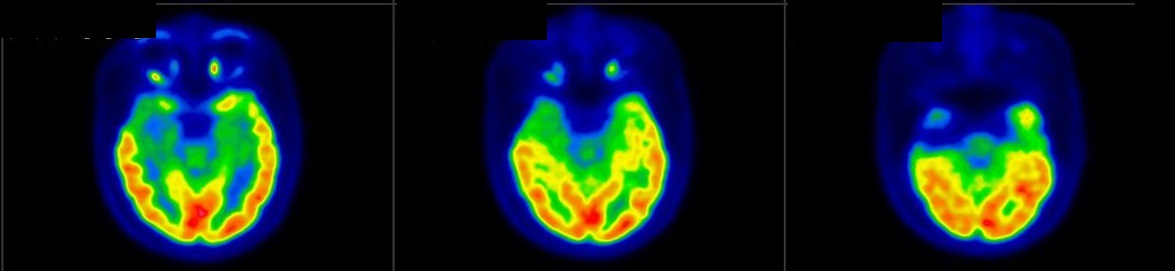

Neurology

![]() [C-11] PIB |

![]() [C-11] Raclopride |

![]() [F-18] DOPA |

PET/CT scans with special tracers can show 3-dimensional images of blood flow and biomolecules deposition in the brain for diagnosis and monitoring the therapy progress of various neurological diseases, such as Alzheimer's, Dementia, Parkinson's disease, Huntingdon's chorea and autism. In 2018, the National Institute on Aging-Alzheimer's Association (NIA-AA) had revised the definition of Alzheimer's Disease (AD) from a syndrome diagnosed by a set of clinical criteria to a biological construct using abnormal protein deposits to define AD as a unique neurodegenerative disease that can lead to dementia. Our hospital has almost 20 years of experience in producing specific tracer to detect abnormal protein deposition in the brain.